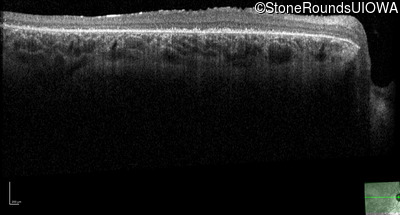

Optical Coherence Tomography - Right - 20/200 +2

Exemplar / OCT Stack

OCT Stack